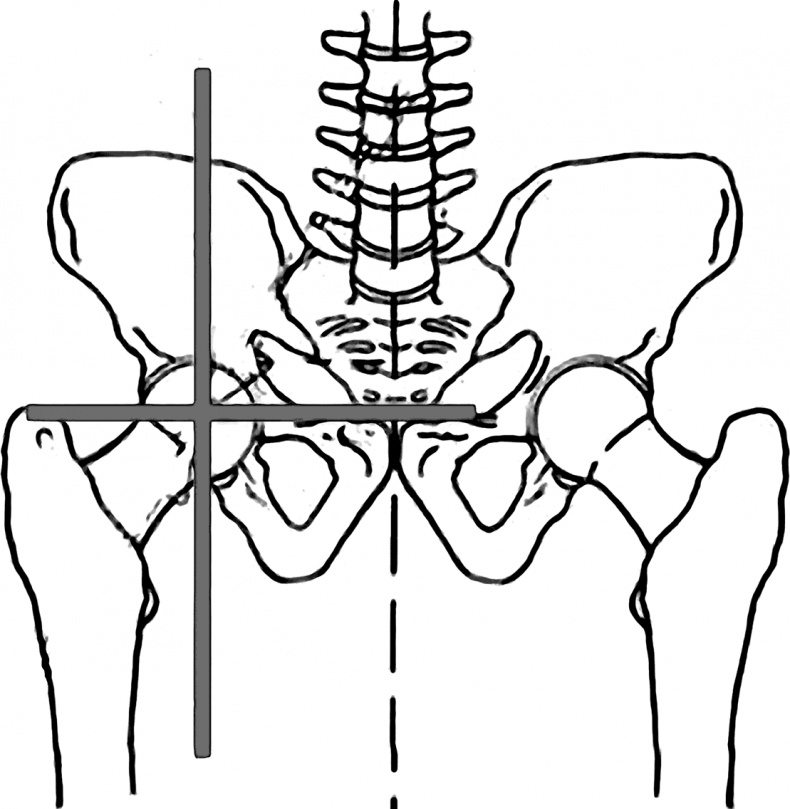

Начальное равновесие тела зависит от положения тазобедренных суставов. Их симметрия обеспечивает баланс всей «ракеты». Иначе она не «полетит».

В идеале вертикальная ось по фронтальной поверхности тела должна проходить строго между ногами, по срединной линии тела и переносице.

Симметрию тазовых суставов во фронтальной плоскости (на виде спереди) можно увидеть на рис. 15.

Рис. 15. Симметрия тазовых суставов

А теперь сравните его с рис. 16 – горизонталь, идущая по ним, перекашивается к левой ноге.

Рис. 16. Асимметрия таза

Видно, что уровень левой стороны (реальной стороны человека) ниже, чем правой. Значит, левая нога больше опирается на землю. Именно здесь нас поджидает дисбаланс под названием «опорная нога». На опорную ногу при ходьбе приходится бо́льшая часть веса человека.